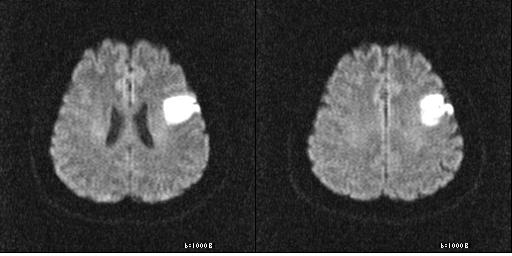

이 질병을 진단하는 검사로는 몇 가지가 이어질 수 있답니다. 뇌졸중에는 뇌출혈과 뇌경색이 있는데, 이 양쪽 모두는 양상이 다르며 무엇이냐에 따라서 치료 절차도 상이하기 때문에 뇌경색 검사방법으로 진단을 정확하게 받는 것이 선행되어야 하고 중요한 부분이라고 할 수 있어요. 우선 뇌경색 초기증상이 보인다면 방문을 하여서 전문가와 상담을 진행하게 되겠고, 진행되는 뇌경색 검사방법으로는 뇌혈관 자기 공명영상, 공명영상 촬영술, 전산화 단층 촬영, 심장 초음파, 경동맥 초음파, 뇌혈관 초음파 등의 방식으로 환자의 현재 상태를 파악하여 치료가 진행되겠죠.